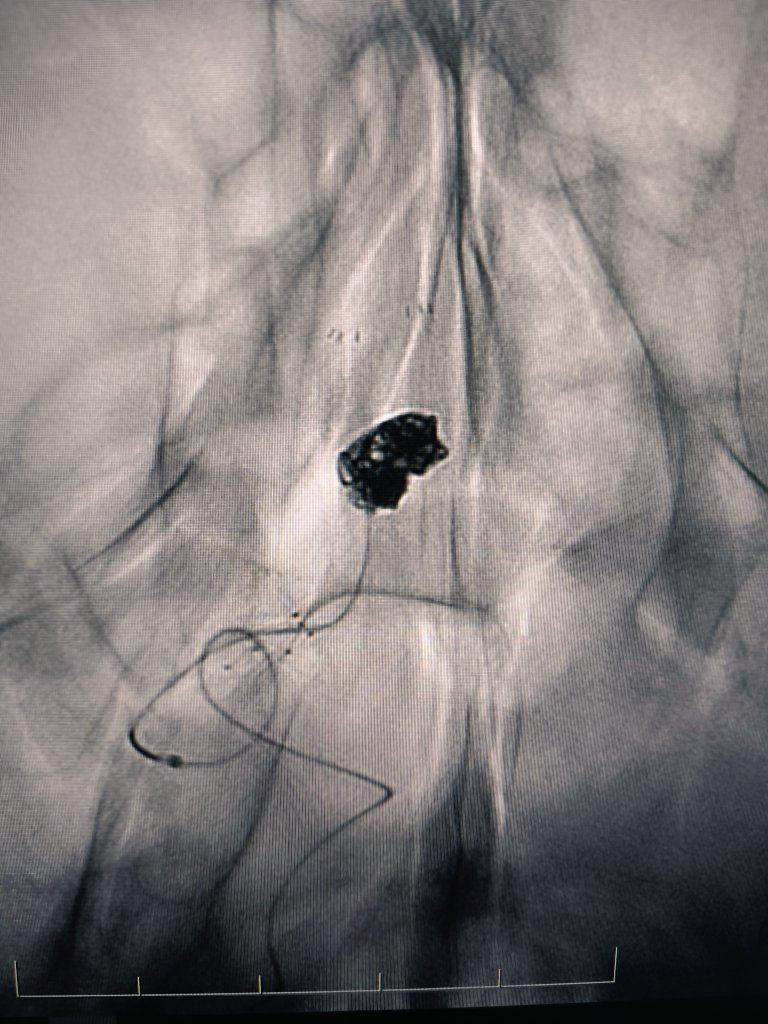

Thrombous at the tip of the iNstroke catheter @CARDIVAGROUP @iVascularGlobal and ICA stenting.

English

Stroke due to left tandem occlusion After crossing the ICA occlusion direct aspiration using nobel 4F iNstroke catheter @iVascularGlobal @CARDIVAGROUP was performed wirh complete recanalization Finally ICA stenting was performed with Wallstent @bostonmedical NIHSS 1 at discharge